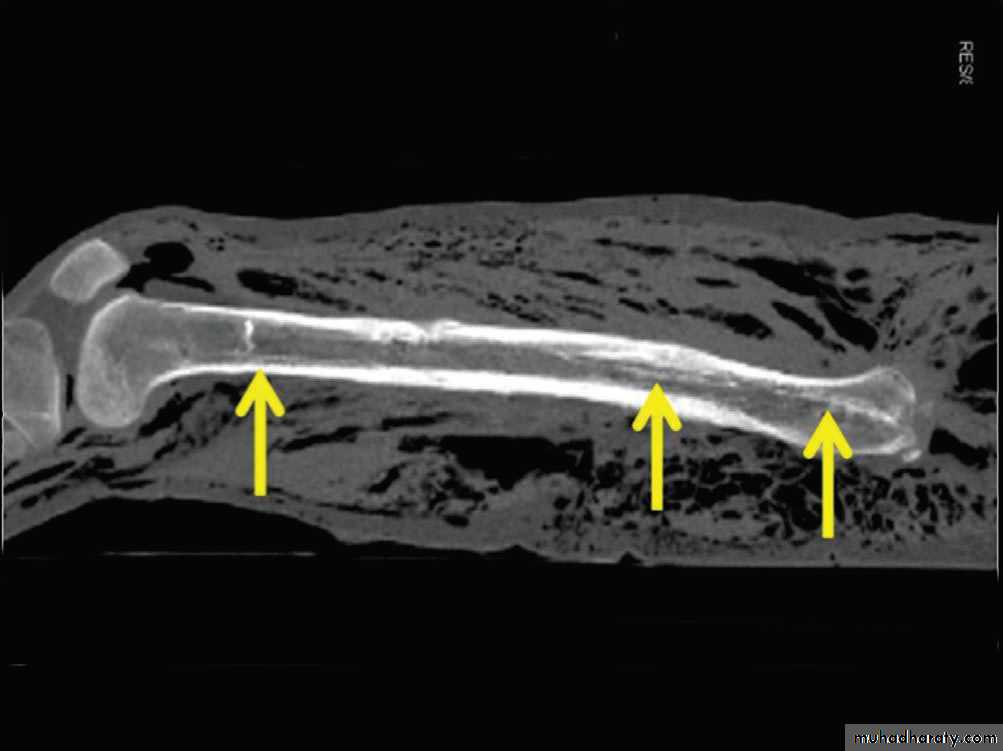

• تقدير العمر من العظام: يستطيع الطبيب ان يقدر العمر بدرجة لاباس بها من الدقة فيما بين الولادة وحتى سن 25 عاما من خلال فحصه المراكزالتعظمية المختلفة وبخاصة تلك التي تظهر في الطرف العلوي, والتي غالبا ما نفضلها على غيرها وذلك لسهولة تحريك الطرف العلوي وبمدى واسع بحيث يتحكم به المصور الشعاعي. يعتمد الطبيب في تقدير العمر على ظهور او التحام مراكز التعظم او كلاهما لمجموعة من العظام, حيث ان هناك اوقات محدد لظهور هذه المراكز والتحامها.

• عمليا يتم تصوير الرسغ والمرفق والكتف لمن يبدوا ظاهرا دون سن العشرين عاما من العمر. ويصور الحرقف لمن بدا في اواسط العقد الثالث من العمر او اقل, والنهاية الانسية للترقوة والتحام القص بالرهابة لمن تجاوز ذلك.

معدل التحام مراكز التعظم:

1) في سن 13-14 سنة تلتحم البكرة بعمد العضد.

2) في سن 14-15 يلتحم راس الكعبرة بالعمد والنتوء المرفقي بالزند.

3) في سن 16-17 سنة تلتحم اللقمة الانسية بعمد العضد.

4) في سن 17-18 تلتحم النهايتان السفليتان للكعبر والزند كل مع عمده.

5) في سن 18-19 يلتحم راس العضد بعمده.

6) وفي سن 25 سنة يلتحم عرف الحرقف بالحرقف والنهاية الانسية للترقوة بالترقوة.